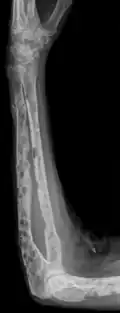

The diagnostic examination of a person with suspected multiple myeloma typically includes a skeletal survey. This is a series of X-rays of the skull, axial skeleton, and proximal long bones. Myeloma activity sometimes appears as "lytic lesions" (with local disappearance of normal bone due to resorption) or as "punched-out lesions" on the skull X-ray ("raindrop skull"). Lesions may also be sclerotic, which is seen as radiodense.[76] Overall, the radiodensity of myeloma is between −30 and 120 Hounsfield units (HU).[77] Magnetic resonance imaging is more sensitive than simple X-rays in the detection of lytic lesions. An MRI may supersede a skeletal survey, especially when vertebral disease is suspected. Occasionally, a CT scan is performed to measure the size of soft-tissue plasmacytomas. Nuclear Medicine Bone scans are typically not of any additional value in the workup of people with myeloma (no new bone formation; lytic lesions not well visualized on nuclear bone scan).

X-ray of the forearm, with lytic lesions -

Humerus with multiple myeloma lesions -

Same humerus before, with just subtle lesions